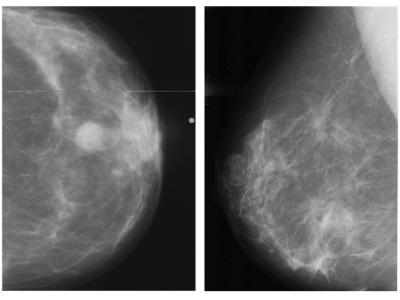

Abnormal mammogram (left) compared with normal mammogram. Image courtesy of the RSNA.

Out of the 747,604 women who underwent screening mammography over an initial 12-month period, the overall cancer detection rate (CDR) was on average 43% higher for enrolled women than for unenrolled women, according to the findings.

All 10 practices saw a substantially higher CDR in enrolled women compared with unenrolled women. Of the overall CDR, researchers further noted a 21% increase in cancer detection that they attributed to the AI program. They credited the remaining 22% increase in cancer detection to the fact that higher-risk patients chose to enroll more frequently.